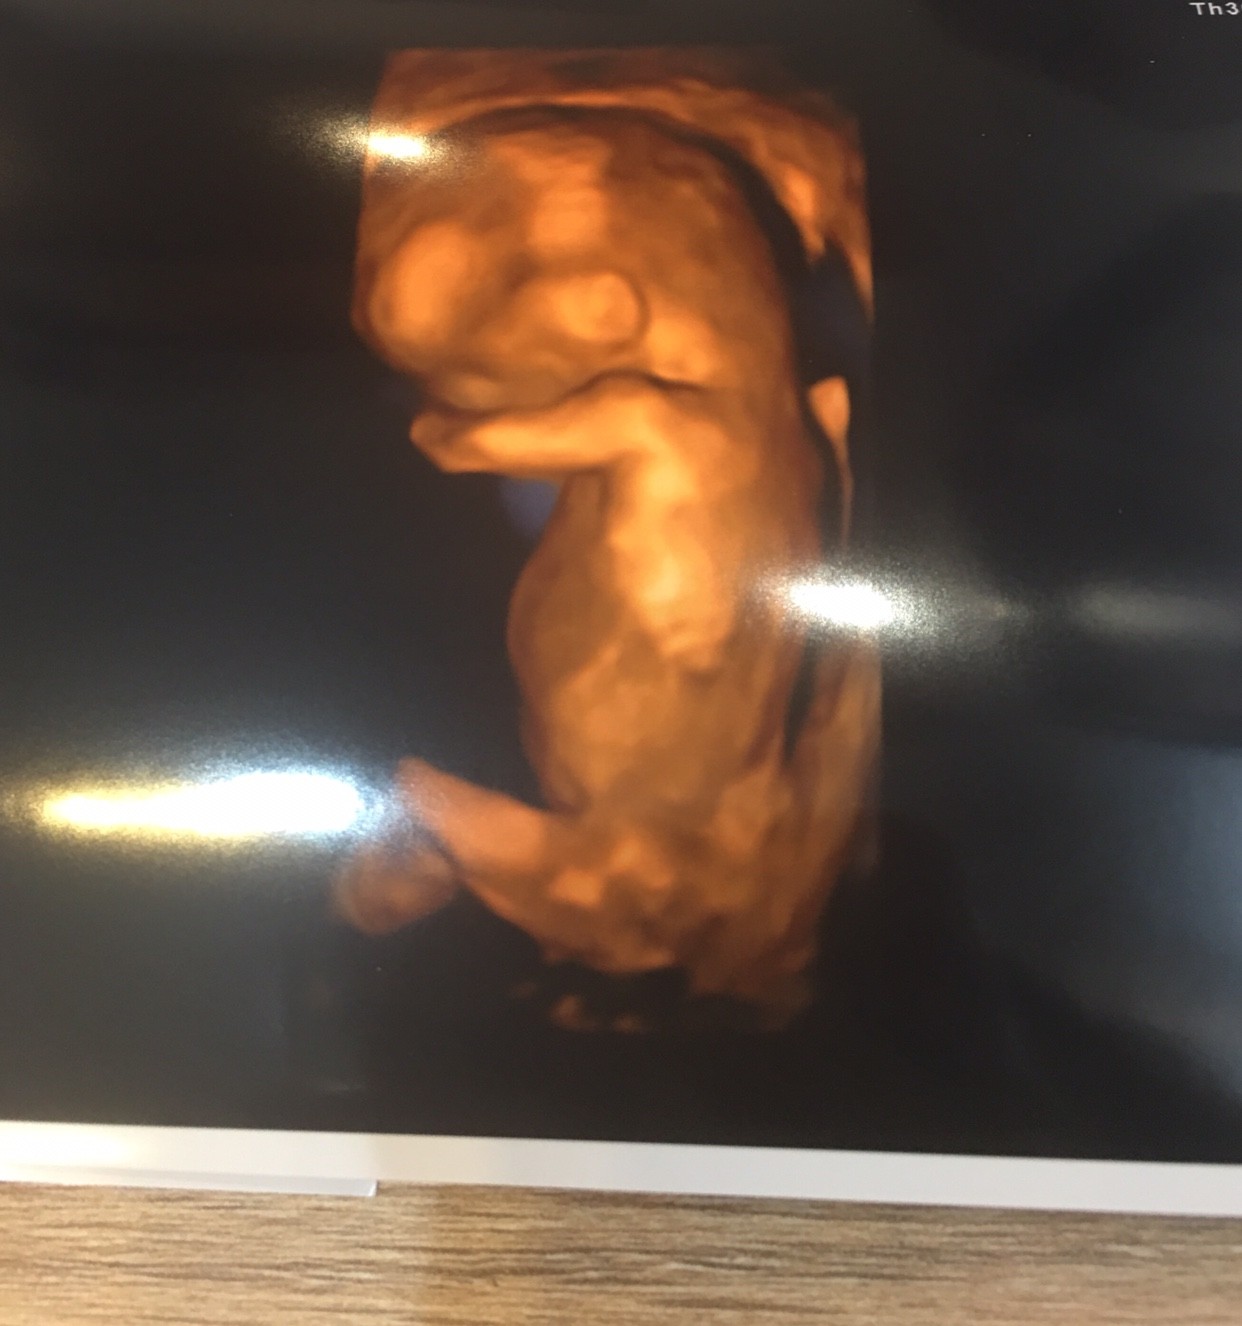

Dziewczyny, ulzylo mi, Zobacz załącznik 1023161juz po prenatalnych. Wszystko dobrze! Dzidzia pieknie rosnie. Lekarz powiedzial, ze na 90% chlopak!

Hej! I ja dziś byłam na wizycie [emoji4] (edit) dziś zaczęty 12 tydzień (11+0) dzidzia 4,6cm. Ale super było widzieć jak dzidziuś się rusza!

IMG_5367.JPG